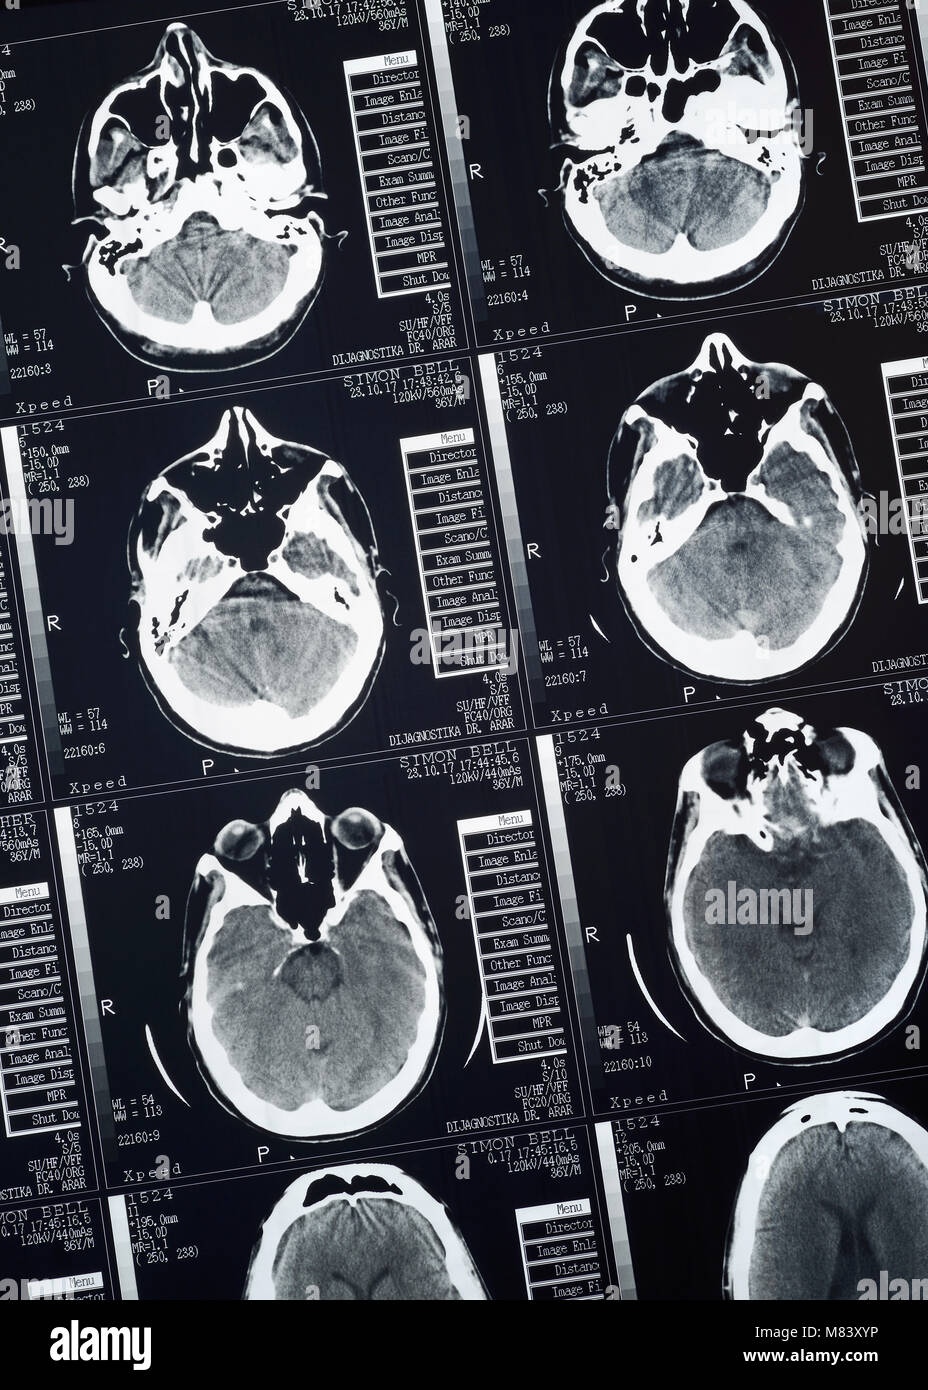

scan brain human tests neuropsychology ct normal photograph

ct gehirn gehirns

brain scan ct drawing sciencephoto anatomy male figure visit

scan brain ct concussion concussions closeup test tests blood shutterstock via